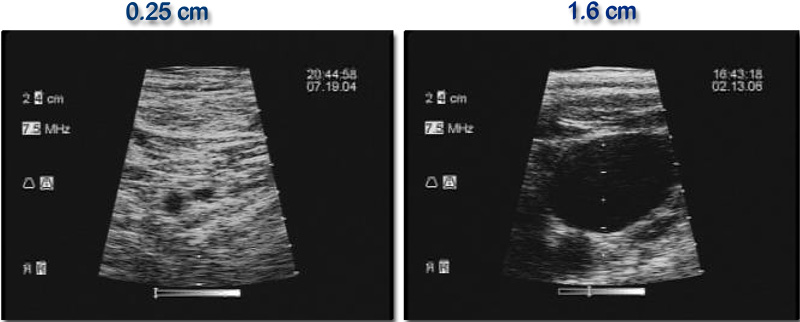

The anatomy of veins and the landmarks that define them are variable and are often impossible to visualize with the naked eye. One prospective study using ultrasound to guide placement found that nearly two-thirds of people have an asymmetry in their internal jugular veins, and the right vein was dominant in less than 70% of cases. Nearly one-quarter of people's veins were 0.4 cm2 or smaller, which can create serious complications (). Other research has found anatomical variations in 8% of internal jugular veins examined with ultrasound (,).